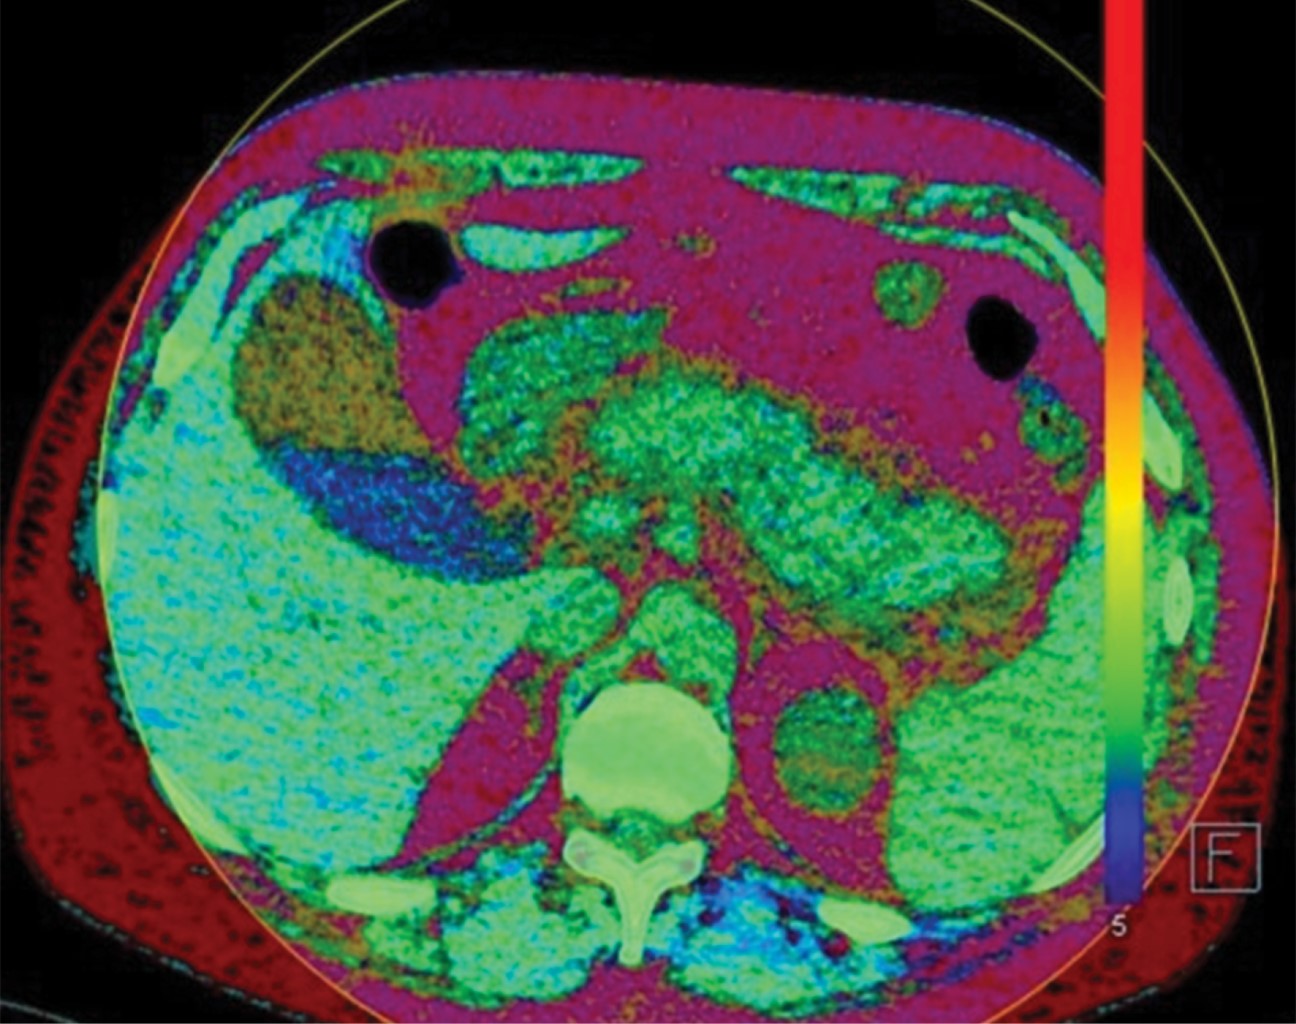

El estudio imagenológico de la litiasis vesicular tiene vital importancia en el manejo de los pacientes con abdomen agudo de los servicios de urgencias.3 La tomografía computarizada de abdomen ha sido establecida como una herramienta primordial de imagenología en el proceso diagnóstico en diversas patologías abdominales y como una herramienta con gran sensibilidad y especificidad en la valoración del abdomen agudo,5 aunque de forma inicial el ultrasonido continúa siendo el estudio de primera elección en pacientes con historia reciente de dolor de tipo biliar, con una especificidad superior a 95% para litos mayores de 2 mm.1,2 En la resonancia magnética la litiasis vesicular se observa mejor en imágenes contrastadas en T2 (Figura 3), e incluso puede ayudar a distinguir entre diferentes tipos de cálculos biliares, los de colesterol tienden a tener mayor intensidad en T1, mientras que los cálculos pigmentados al igual que los de colesterol tienden a ser hipointensos en secuencias en T2, lo cual tiene implicaciones terapéuticas.2,6